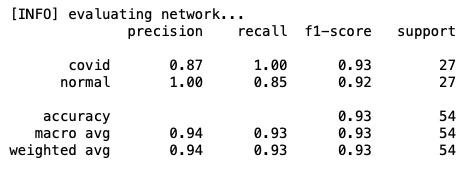

使用20个阶段和初始参数,结果看起来非常有趣,验证数据的精度达到100%!让我们绘制精度图表,评估训练的模型,并查看混淆矩阵:

precision recall f1-score support covid 0.96 1.00 0.98 27 pneumo 1.00 0.96 0.98 27 accuracy 0.98 54 macro avg 0.98 0.98 0.98 54weighted avg 0.98 0.98 0.98 54

混淆矩阵

[[27 0] [ 1 26]]acc: 0.9815sensitivity: 1.0000specificity: 0.9630

通过训练模型(初始选择超参数),我们得到:

- 100%敏感度,也就是说,对于COVID-19阳性(即真正例)的患者,我们可以在100%的概率范围内准确地确定他们为“COVID-19阳性”。

- 96%特异性,也就是说,在没有COVID-19(即真反例)的患者中,我们可以在96%的概率范围内准确地将其识别为“COVID-19阴性”。

结果完全令人满意,因为只有4%的患者没有Covid会被误诊,但与本例一样,肺炎患者和Covid-19患者之间的正确分类是最有益处的,因此我们至少应该对超参数进行一些调整,再次进行训练。